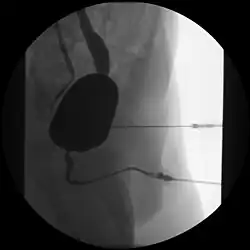

Unauffällige männliche Urethra, aber beidseitiger Reflux

Im Gegensatz zur Urethroskopie im Rahmen einer Zystoskopie als optisches Verfahren mit Hilfe eines Endoskopes erfolgt die Urethrographie als Röntgen-Untersuchung mit Durchleuchtung und Gabe von Kontrastmitteln.

Die Untersuchung kann in Richtung des Urinflusses (antegrad) im Rahmen eines Miktionszystourethrogrammes erfolgen oder rückwärts (retrograd) als Retrograde Urethrographie (RUG) mit Darstellung der Harnblase.[1]

Bei männlichen Patienten erfolgt eine etwa 45° Schräglagerung und Abspreizung des Oberschenkels, so dass die Urethra möglichst ohne knöcherne Überlagerung darstellbar wird. Über die äußere Harnröhrenmündung an der Penisspitze wird über einen Katheter ein Kontrastmittel injiziert.